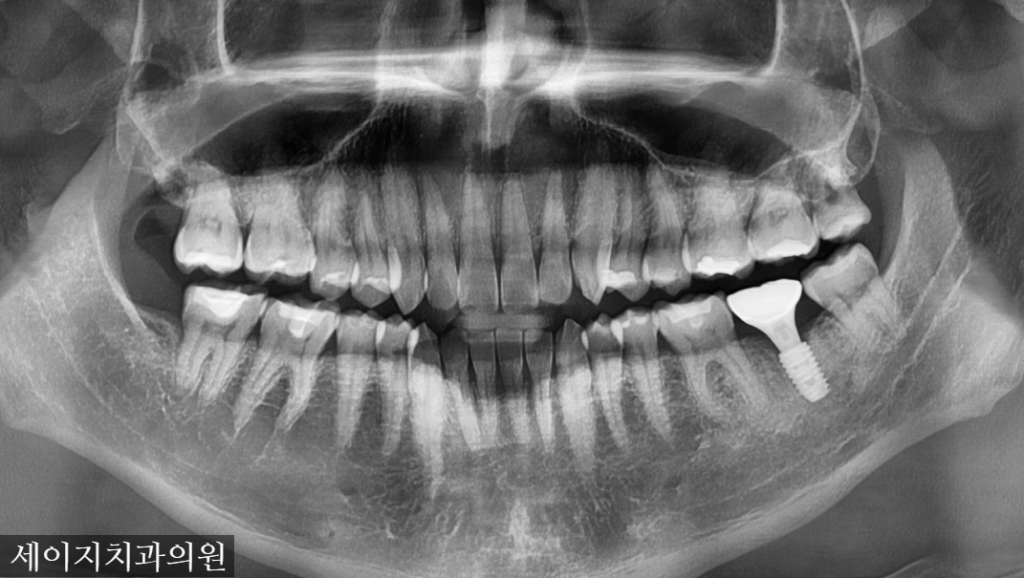

2023. 12. 02

CT를 이용한 기존 모의 수술과 비슷한 결과값을 얻었으며 수술당시 광범위한 뼈이식을 통해 골조직을 재건해드렸습니다.

뼈이식은 이식재의 선택부터, 연조직의 핸들링까지 숙련된 치과의사에게 시술받아야 합니다. 감염으로부터 보호하기 위해 적절한 조치가 이루어져야 하며, 환자의 통증조절을 위해서도 여러가지 임상적인 노하우가 필요합니다.